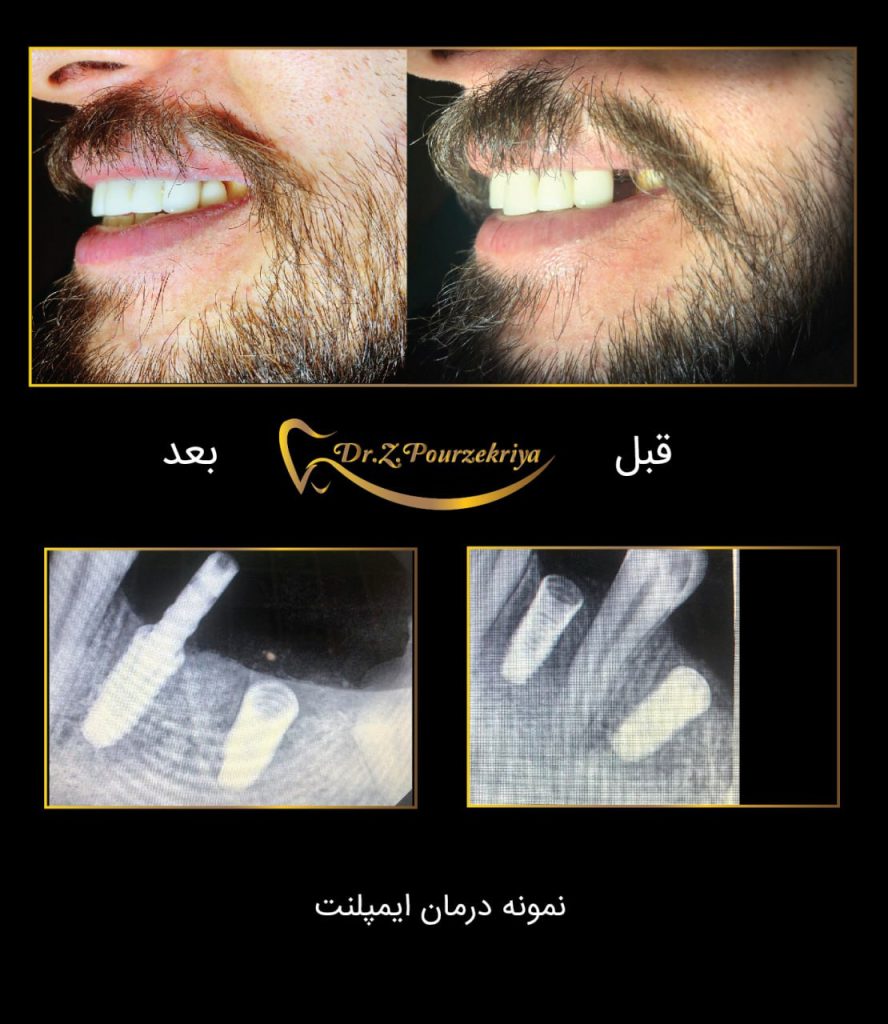

بازسازی دندان ها با روش برتر ایمپلنت

راهی برای زیبایی ، سلامتی

و لبخندی درخشان

بازسازی دندان ها با

روش برتر ایمپلنت راهی برای زیبایی

سلامتی و لبخندی درخشان

ایمپلنت دندان راه حل نهایی بی دندانی

ایمپلنت دندانی یک روش درمانی است که از طریق جایگزینی دندان طبیعی با دندان مصنوعی میباشد. این دندان ها از موادی مانند فلز تیتانیوم ساخته شدهاند و به استخوان فک یا لثه متصل میشوند.

- بازگردانی زیبایی و عملکرد با ایمپلنت دندان

- سلامتی و زیبایی با ایمپلنت

نمونه های درمان

دکتر زکیه پور ذکریا، جراح دندانپزشک و ایمپلنتولوژیست :

ورضایت مراجعین برایم بزرگترین تبلیغ محسوب میشود